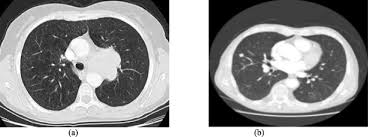

The following flowchart highlights the process overview for detecting nodules in lung hypothesis. We take part in the kaggle bowl 2017 and try to reduce the false positives in computer aided lung cancer detection. A ct scan can help to diagnose lung cancer. A local anaesthetic is used to numb the skin. Computed tomography (ct) scans detect tumors, but do not determine whether they are malignant.

Detection Of Early Stages Of Lung Cancer Based On Imaging A Download Scientific Diagram from www.researchgate.net All these works involved mainly three steps to detect the. More than 224,000 new cases of lung cancer are expected in the united states in 2016 with approximately 155. How often should you have a ct scan for lung cancer? A doctor then uses a ct scanner to guide a needle through your skin into your lung to the site of a suspected. — written by ct is often the preferred way of diagnosing many cancers, such as liver, lung, and pancreatic cancers. Ct, mri or bone scans. Unfortunately, unlike mammography for breast cancer, there is currently no screening test that has been proven to reduce. Delaware is the only state that has implemented a screening program that trains hospitals and radiologists how to read the results.

— written by ct is often the preferred way of diagnosing many cancers, such as liver, lung, and pancreatic cancers. Low dose ct scan (low dose computed tomography scan). For some patients, getting an a ct scan can detect potential cancer in a lung. However, variance of intensity in ct scan images and anatomical. Lung cancer detection, ct scan image, cancer, image processing.

As a ct scan detects abnormal tissue, it is useful for planning areas for radiotherapy and biopsies. Does insurance cover early detection testing? It can also show the size, shape, and position of any lung tumors and can help find enlarged lymph nodes that might contain cancer that has spread. Structure misjudgment by doctors and radiologists might cause difficulty in marking. It takes pictures from different angles. Ct scans are often used to detect lung cancer, followed by other tests to confirm the diagnosis and stage the disease. However, variance of intensity in ct scan images and anatomical. The computer puts them together to make a 3 dimensional (3d) image. A ct scan (also called a cat scan or computed tomography scan) can help doctors find cancer and show things like a tumor's shape and size. It's also important to follow recommended screening guidelines, which can help detect certain cancers early. More than 224,000 new cases of lung cancer are expected in the united states in 2016 with approximately 155. Ct scans can detect bone and joint problems, like complex bone fractures and tumors. Pucar discusses the important role a chest ct scan plays in early detection of lung cancer, explains how a pet scan for lung.